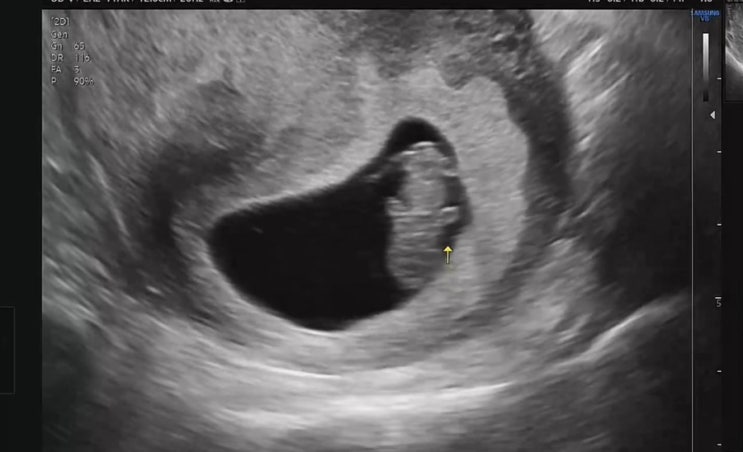

입덧일기-9주 10주 (피비침이슈)

끝이 안보이는 터널을 지나는 느낌 내 변화무쌍한 입덧에 유경험자들도 의아해한다 그래도 뭐 잘먹는거 하...

지난 10월 화학적 유산 후 다시 찾아와준 아이! 나 평소에 층간 소음도 전혀 못느끼는 맹장염 왔을때도 3일...